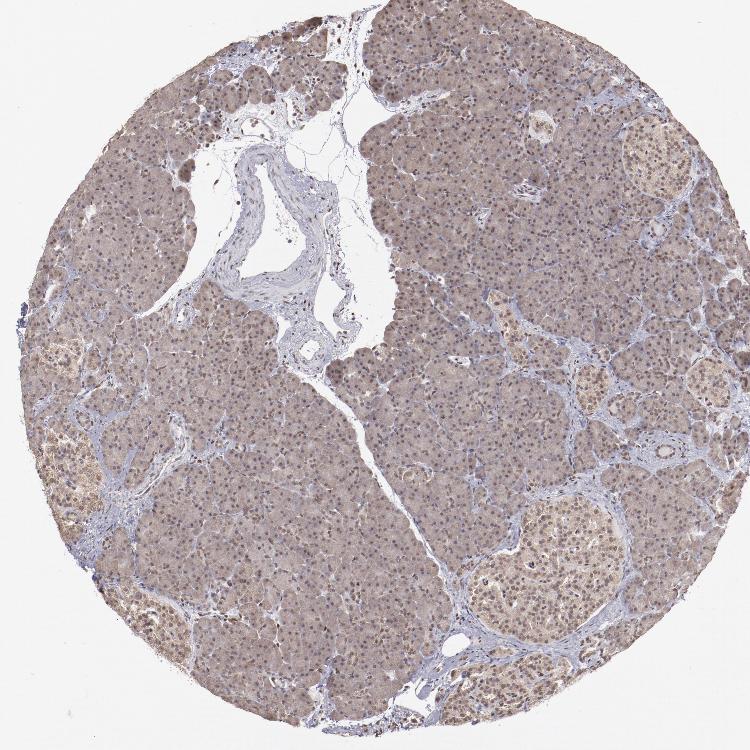

PANCREAS - Antibody stainingi

Antibody staining in the annotated cell types in the current human tissue is reported as not detected, low, medium, or high, based on conventional immunohistochemistry profiling in selected tissues. This score is based on the combination of the staining intensity and fraction of stained cells.

Each image is clickable and will lead to virtual microscopy that enables deeper exploration of all samples and also displays staining intensity scores, fraction scores and subcellular localization as well as patient and tissue information for each sample.

Antibody HPA001759Antibody CAB004318

Exocrine glandular cells MediumLow

Pancreatic endocrine cells Medium-